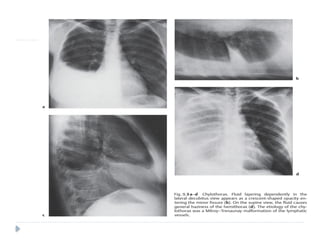

 Lateral decubitus position:

 Fluid collects between the lateral chest wall and

the lung, producing a band of opacification

which may enter the minor fissure.

 Chest radiographs show a biconvex, spherical, or elliptical

homogeneous opacity.